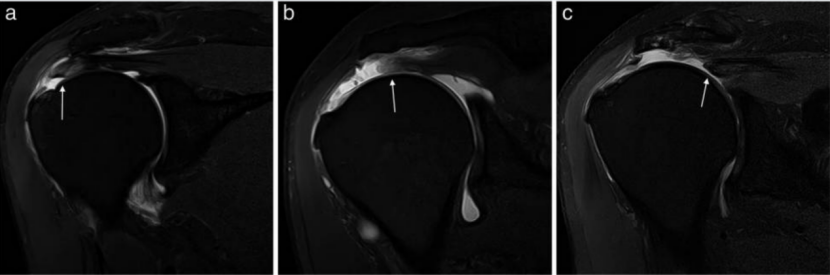

图 1:全层撕裂模式。a-c 不同全层撕裂模式的示意图:新月形、U 形和 L 形。d-f 轴位脂肪抑制 PD 加权 MRI 关节造影显示不同模式(箭头所示)。图源:文献 3

图 5:冈上肌全层撕裂的不同回缩阶段(箭头所示)。斜冠状位脂肪抑制 PD 加权 MRI 关节造影显示:a、完全全层撕裂伴少量回缩;b、全层撕裂伴纤维回缩至肱骨头顶点上方。斜冠状位脂肪抑制 PD 加权 MRI 显示:c、肌腱纤维回缩至肩胛盂上缘上方。图源:文献 3